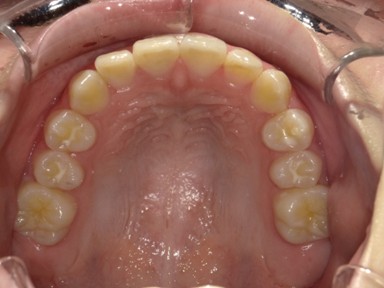

| 主訴 | 生えてきた下の永久歯が曲がっている。これから生えてくる歯も並ぶか心配。 |

| 治療内容 | マイオブレース(J1 → J2 → K3 → T4)と拡大床(BB1)を使用しました。 口腔周囲筋トレーニングも併用しました。 (抜歯:なし、ワイヤー矯正:使用せず) |